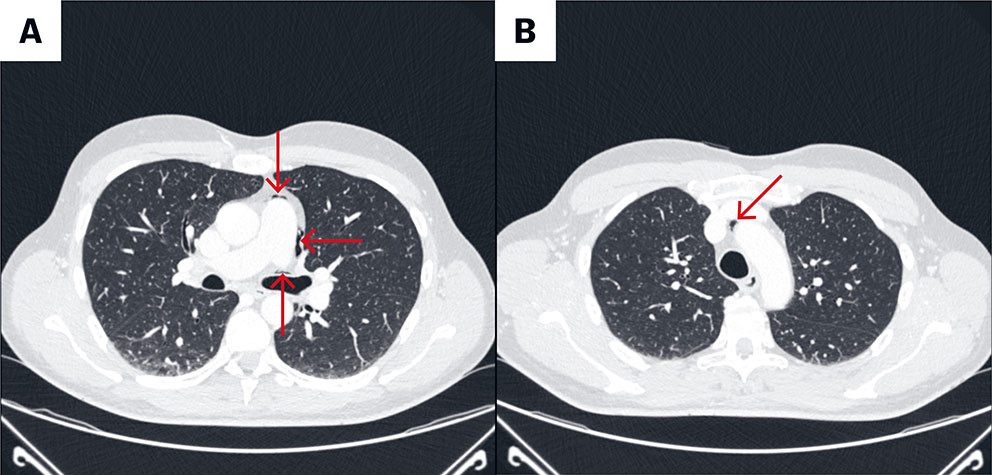

CT av toraks og abdomen/bekken ble tatt rett etter innkomst for å se etter postoperative komplikasjoner. Den viste gass subkutant, mellom fascielagene i bukveggen, i mediastinum, intraperitonealt ved lever samt retroperitonealt (figur 1a og b og figur 2). Det var ingen synlig gass i pleura, og det var ingen tegn til blødning.

På grunn av den spredte gassen og inngrepets art, var iatrogen tarmskade den fremste tentative radiologiske diagnosen. CT-bildene ble sett på av vakthavende radiolog sammen med vakthavende gastrokirurg. Pasientens symptomer var synkope og lett respirasjonspåvirkning, men ingen magesmerter. Buken var bløt uten peritonisme. Til tross for lett feber og leukocytose, var den kliniske vurderingen at tarmskade var mindre sannsynlig. Vi mistenkte derimot at CO2-gassen fra laparoskopien hadde vandret, og at symptomene var forårsaket av capnomediastinum.